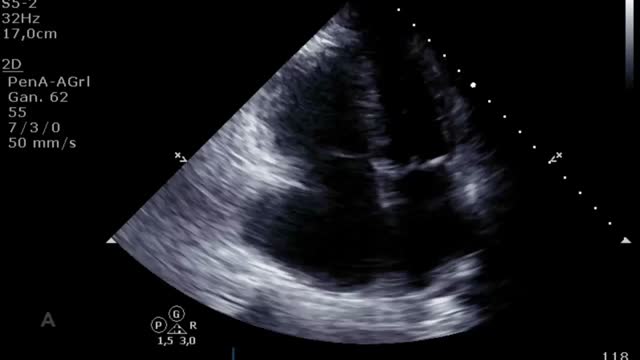

Por último, muchos de los pacientes con ECMO VA pueden tener algún otro dispositivo de asistencia ventricular izquierda (BCIAo, Impella®) como medida de descarga ventricular34 y de los que también deberemos controlar su posición y funcionamiento12. En el caso del BCIAo, mediante ETT/ETE podremos observar el inflado del balón a nivel de la aorta descendente con su extremo distal a nivel del nacimiento de la subclavia izquierda (suplementario 17). El Impella® se puede explorar tanto por ETT (paraesternal de eje largo o apical de 3 cámaras) como por ETE (mediesofágico 120°) y debemos observar el dispositivo entrando desde la aorta ascendente y el inlet o zona de succión a 3-4cm de la válvula aórtica35,36 (fig. 4 y suplementario 18).

El destete supone un proceso de descenso gradual (500ml cada 15-20min) del soporte de la ECMO VA de manera que se restablece progresivamente la precarga en el corazón. Para ello el paciente debe estar adecuadamente anticoagulado. Evaluaremos la repercusión hemodinámica (PVC, PAM y diferencial, SvO2, SatO2) y ecocardiográfica (FEVI, IVT, onda E, onda E’ o S’ del anillo mitral lateral) que tiene hasta un nivel (normalmente 1-1,5l/min) que nos indique que el paciente puede tolerar la retirada de la asistencia. Durante esta, evaluaremos que mantiene e incluso aumenta la FEVI por encima del 25-30%, la IVT por encima de 10cm y la onda S’ de más de 6cm/s (fig. 5 y suplementario 22). Junto con ello, también evaluaremos el comportamiento de las cavidades derechas (desplazamiento sistólico del plano del anillo tricuspídeo>16cm, S’>10cm/s y tamaño VD) y la posible aparición de signos de hipertensión pulmonar (aumento de la velocidad pico de la insuficiencia tricuspídea) que predigan un fracaso de VD38–40.